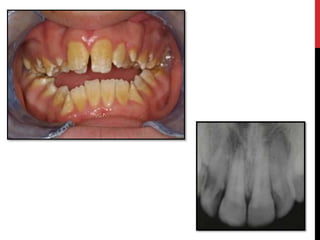

Hypocalcified amelogenesis imperfecta

 Enamel matrix is laid down properly but no significant

mineralization occur.

Hypocalcified amelogenesis imperfecta Enamel matrix is laid down properly but no significant mineralization occur.

• #33 The enamel is softer than normal and tends to chip of from the underlying dentin. Radiographically the affected enamel exhibits a radiodensity that is similar to dentin.